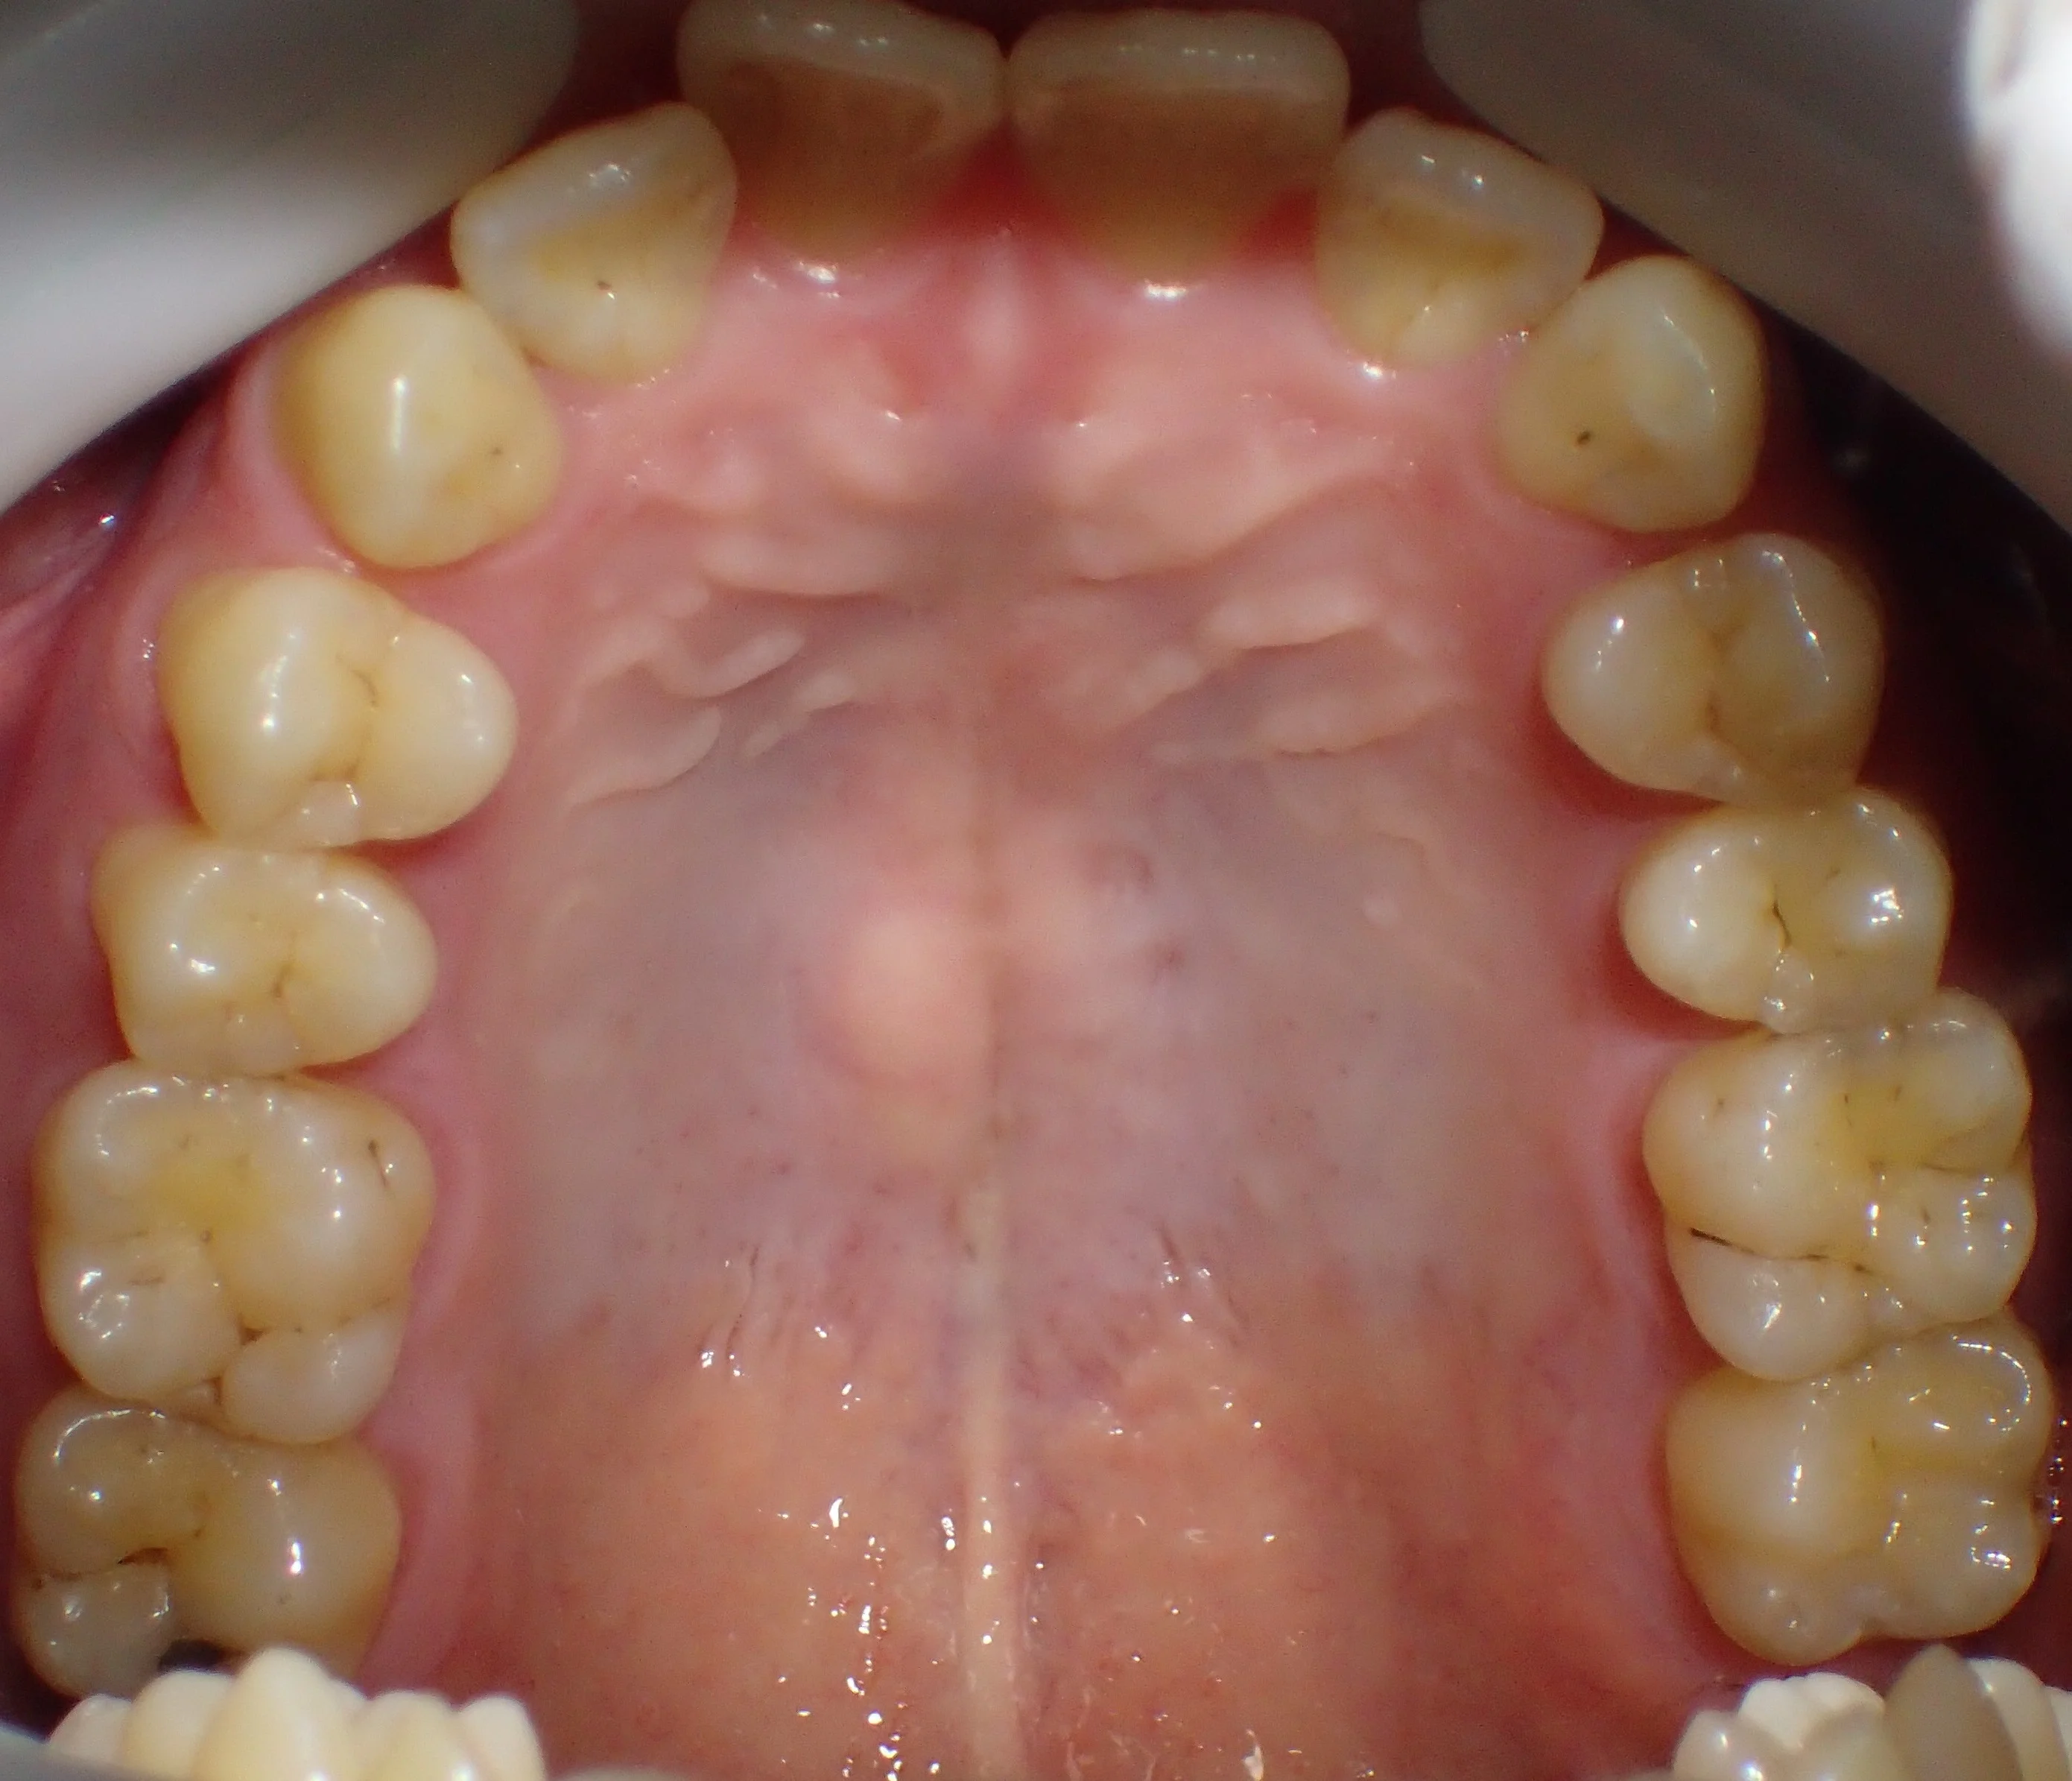

ダイレクトボンディングによる治療

まだ坂寄歯科医院には全顎的にダイレクトボンディングで治療した症例がありませんので、前の医院にて治療を完了された方の写真を載せたいと思います。 写真が下手なのは勘弁してください・・・。 鏡面像で反転済みです。 「向こう側からこちらに向かって口…

続きを読む →